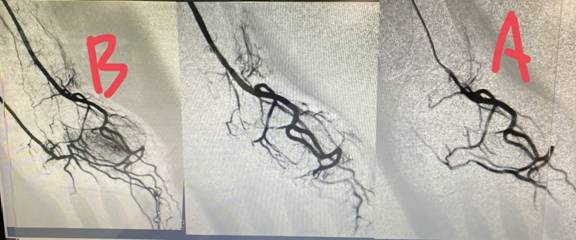

圖三:因職業傷害無法工作的廚師,右手新生的異常微細血管(圖左,標注為B),處理過程中異常微細血管逐漸消失(圖中),手術過異常微細血管都被不見(圖右,標注為A)